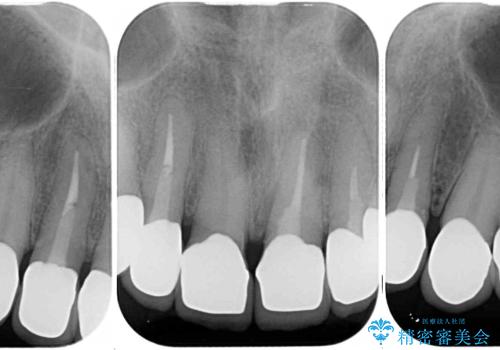

- コンポジットレジンやクラウンなど、様々な医院で治療を受けたために、統一感がなくなってしまった前歯を綺麗にしたいとのことで来院された患者様です。

当初は前歯6歯をオールセラミッククラウンで補綴する予定でしたが、前歯が綺麗に仕上がったことで、奥歯まで延長して補綴することとしました。

黄ばんだ前歯や白すぎたクラウン、プラスチックの継ぎ接ぎなどを全てオールセラミッククラウンの統一感のある前歯に仕上げました。